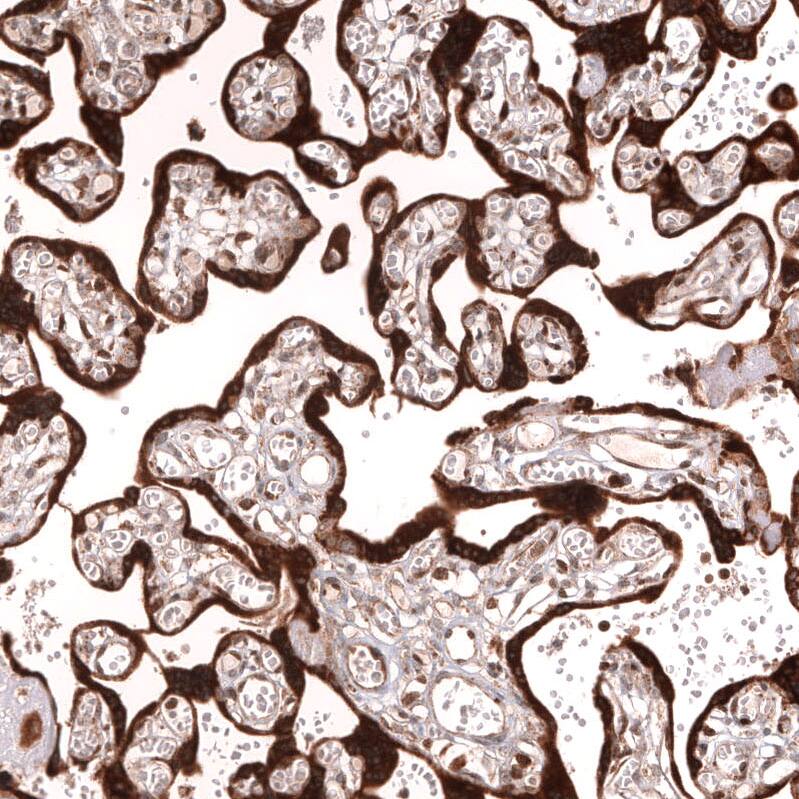

Immunohistochemistry-Paraffin: IL-33 Antibody (CL13438) [NBP3-24558]

Staining of human placenta shows strong cytoplasmic positivity in trophoblastic cells.